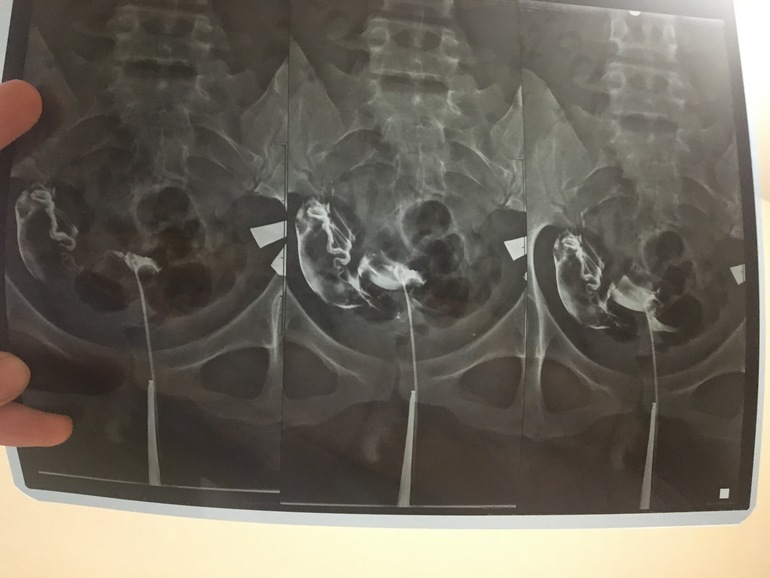

Ну в общем, проверили мне трубы в пятницу. Оказалось что проходима только одна. Я вот смотрю на свой снимок и переживаю, а вдруг там тоже спайки, а вдруг яйцеклетка не пройдёт. Помимо трубы, у меня ещё и СПКЯ и у мужа подвижность плохая (но над этим мы работаем).

Может ли быть такое что после проверки она пробьётся? Кто шарит вот мой снимок, кто что скажет.

Ещё не могу почему на снимке полость матки такая маленькая (